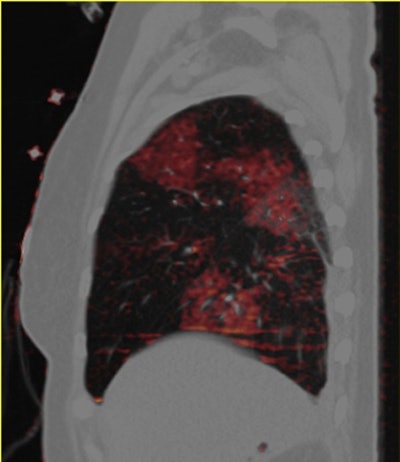

Dual-energy CT enables the selective display of iodine distribution within the pulmonary parenchyma following contrast-enhanced pulmonary CT angiography, which in turn permits the calculation of perfusion defect (PD) size in patients with suspected PE.

Depending on the shape and pattern of the defects at dual-energy CT, perfusion defects due to PE can generally be distinguished from, for example, patchy defects signaling other pathologies of the lung parenchyma, Bauer said.

The researchers measured perfusion defect size in the lung parenchyma caused by PE on dual-energy iodine distribution maps, and expressed it in two ways: as absolute quantification (VolPD in mL) and relative to the total lung volume (RelPD in %).

"When we did lung perfusion, the analysis was restricted to the field-of-view," which is limited due to the smaller second detector on the dual-source CT scanner, he said. As a result "there were 40 patients with no coverage loss, eight patients with up to 5% coverage loss, and five patients with up to about 10% of coverage loss in the peripheral" areas of lung parenchyma, he said.

| Patient with bilateral segmental and subsegmental PE and large perfusion defects on dual-energy iodine distribution maps. All images courtesy of Dr. Ralf Bauer. |